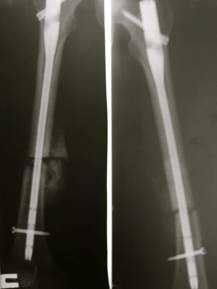

На операции: в области обеих бедренных костей определяются костные мозоли с патологическим разрастанием фиброзной ткани. Определяется незначительная подвижность костных отломков. Выполнена остеотомия бедренных костей на уровне костной мозоли, удалена фиброзная ткань (Рис. 3). С помощью разверток произведено вскрытие костно - мозгового канала в проксимальных и дистальных отломках. Произведена репозиция отломков и фиксация интрамедуллярными универсальными бедренными штифтами Aesculap. Дистальные блокирующие винты установлены в динамические отверстия (Рис. 4). Разница в длине нижних конечностей устранена. Выполнено послойное ушивание послеоперационных ран отдельными узловыми швами. Асептические повязки. Кровопотеря составила 300 мл.

Рис. 4. Послеоперационные рентгенограммы пациентки С., 25 лет